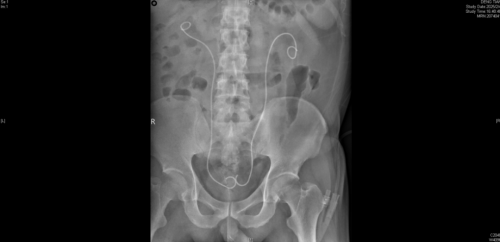

术前CT片显示双侧肾结石、双输尿管结石导致双肾积水

术后复查,双侧输尿管支架管留置,梗阻解除